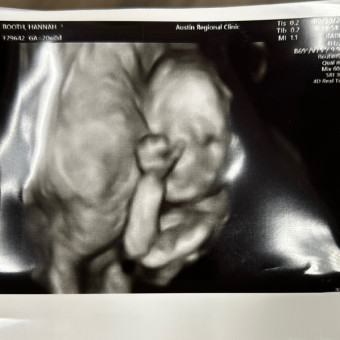

hannah, alec & baby rosemary 🤍Feeding